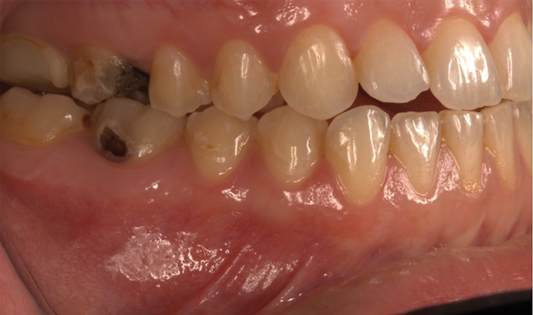

The effects of ENDS on caries activity has not been well established. A few studies suggest that vaping may increase the cariogenic potential, pointing to increased acid production from propylene glycol heating, sweet flavors, sucrose, viscous aerosol, higher bacterial attachment to tooth surface, increased biofilm formation, decreased enamel hardness, and dry mouth (Figure 1 and Figure 2).28

Fig 1. and Fig 2. Multiple carious posterior teeth after use of e-cigs. Fig 1: Gross caries on maxillary and mandibular right first molars; Fig 2: Gross buccal caries on a mandibular left first molar. (Reprinted with permission from Journal of Esthetic and Restorative Dentistry.28 Copyright 2020, John Wiley and Sons).

mandibular right first molars; Fig 2: Gross buccal caries on a mandibular left first molar. (Reprinted with permission from Journal of Esthetic and Restorative Dentistry.28 Copyright 2020, John Wiley and Sons)